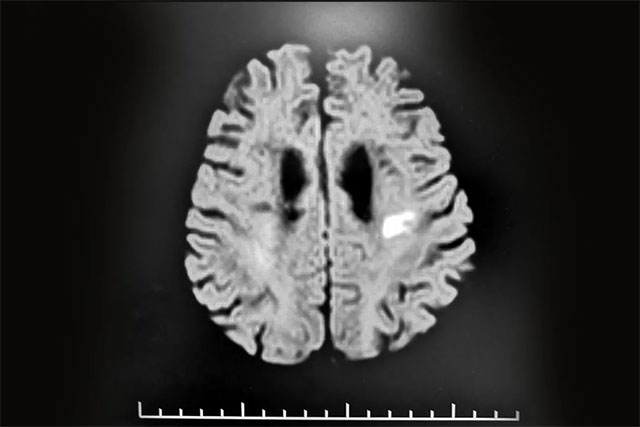

張靜波主任還接診了這樣一位腦;颊撸航衲7月初,68歲的程先生(化名),第一次患腦血管疾病,并以腦梗死形式發(fā)病,根據(jù)其頭部CT影像結(jié)果所示,其腦梗病灶并不是很大,但患者入院不久后就出現(xiàn)了一些精神障礙,表現(xiàn)為癡呆、答非所問(wèn),自言自語(yǔ),記憶力減退,有時(shí)罵人,甚至有暴力的行為,這讓家人不知所措。

▲ 患者頭部CT所示:其腦梗病灶并不嚴(yán)重

對(duì)此,張靜波主任解說(shuō),一般正常情況,只有當(dāng)患者一次出現(xiàn)大面積腦梗,或其腦組織損害一次性超過(guò)80ml以上,才可能出現(xiàn)癡呆等表現(xiàn)。但患者程先生其腦梗病灶面積實(shí)際并不是很大,這就無(wú)法解釋他出現(xiàn)癡呆、罵人及記憶力減退等精神癥狀。